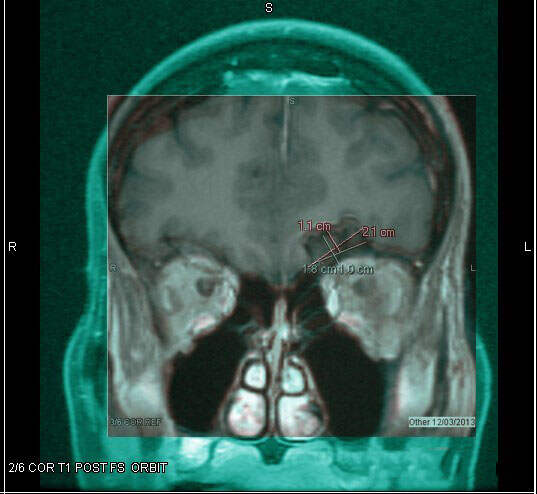

2017年4月22日,蘋果近期悄悄完成了該公司史上最酷之一的招聘活動(dòng),據(jù)了解,蘋果把麻省理工學(xué)院(MIT)的高材生——曾在自己被診斷患有腦腫瘤之后進(jìn)而用3D技術(shù)打印出自己腦腫瘤的博士生史蒂文·基汀(Steven Keating)招致麾下。

2015年,基汀因展示了自身在深入理解人類腦腫瘤方面的科學(xué)實(shí)驗(yàn)而名聲大噪。當(dāng)時(shí),基汀向Vox媒體表示,他搜集了約75GB的有關(guān)他自身健康信息相關(guān)的數(shù)據(jù),其中包括他自身的腫瘤病理切片和醫(yī)療信息等在內(nèi)的多種數(shù)據(jù)。

在此次賽智生物網(wǎng)絡(luò)年度大會(huì)上,基汀談?wù)摿瞬∪嗽诰酆纤麄冏陨磲t(yī)療數(shù)據(jù)方面的困難?;”硎荆罱K選擇去醫(yī)學(xué)院,其中的部分原因就是為了能夠研究自身的人體器官,從而為業(yè)界探索出一條簡捷通道。據(jù)一位出席賽智生物網(wǎng)絡(luò)年度大會(huì)的人士透露,基汀在大會(huì)上還聲稱,他曾以圣誕樹裝飾品的形式將他的腦腫瘤3D打印模型展示給家人看。